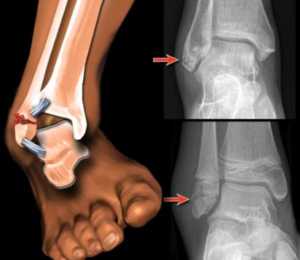

Наиболее часто отечность возникает, если человек сломал лодыжку или после перелома пятки. Срастание костей в этих местах занимает более длительный период, ведь на пятку и лодыжку приходится большая нагрузка.

Непрерывный обмен между тканевой жидкостью и кровью происходит через капилляры (мелкие кровеносные сосуды). Попадание жидкости в окружающую ткань через стенки кровеносных сосудов называется «транссудация». Если из сосудов в окружающую ткань выделяется значительное количество жидкости, а обратное ее всасывание затруднено или остановлено, появляется отек. Причиной обратного всасывания жидкости в кровь становятся повреждения связок, мышц и других тканей, нарушение их нормального функционирования в результате переломов. Чаще всего опухание в месте перелома возникает не сразу, оно имеет нарастающий характер и распространяется только в области поврежденного участка. При внутрисуставных, оскольчатых переломах ног, травмах со смещениями опухоль может также распространяться на всю конечность. Подобные травмы сопровождаются потерей чувствительности ткани, резкими ограничениями движений, болезненными ощущениями.

В некоторых случаях в процессе реабилитации больного после снятия гипса наблюдается отек ноги. Подобное явление носит название «лимфостаз». Оно вызывается нарушением баланса образования лимфы и ее оттока. Лимфостаз может наблюдаться и при переломе ноги, если травма сопровождается повреждениями кровеносных сосудов и лимфатических узлов. Кроме уплотнения тканей, в данном случае наблюдается также утолщение кожи. Лимфатический отек может повлечь за собой ряд осложнений (язвы, слоновая болезнь, фиброз, кистоз). Нога отекает после перелома и после получения серьезных травм особой тяжести. Такие переломы могут быть открытыми, они сопровождаются растяжением или повреждением связок. В результате повреждений суставы опухают, отеки приобретают особую величину.

Какой бы ни была причина появления отеков ноги после перелома, получить консультацию специалиста нужно в ближайшее время, что позволит избежать неприятных последствий. Чтобы точно определить, почему отекает нога, назначается рентгенография и ультразвуковое исследование сосудов конечности.

После травмы лодыжки и пятки (голеностопа) суставы всегда опухают. Подъем крови и лимфы вверх с самого нижнего уровня тела – процесс, требующий усилий организма. Когда происходит перелом голеностопного сустава, кости из-за нагрузки срастаются медленно, и дренажная система не справляется с отводящими функциями.

При тяжелых переломах с разрывами связок отеки порой приобретают угрожающие формы. Нога значительно увеличивается в размере. Медики называют такой симптом слоновьим. Несвоевременное обращение к врачу влечет хронические застои.

Отекает нога после сложного перелома и от защемления сдвинутой костью крупного сосуда. В этом случае необходима срочная медицинская помощь. Промедление приведет к необратимым атрофическим процессам. Врач решает, достаточно гипсовой повязки либо нужна операция по возвращению кости на место и закреплению ее металлическими фиксаторами.